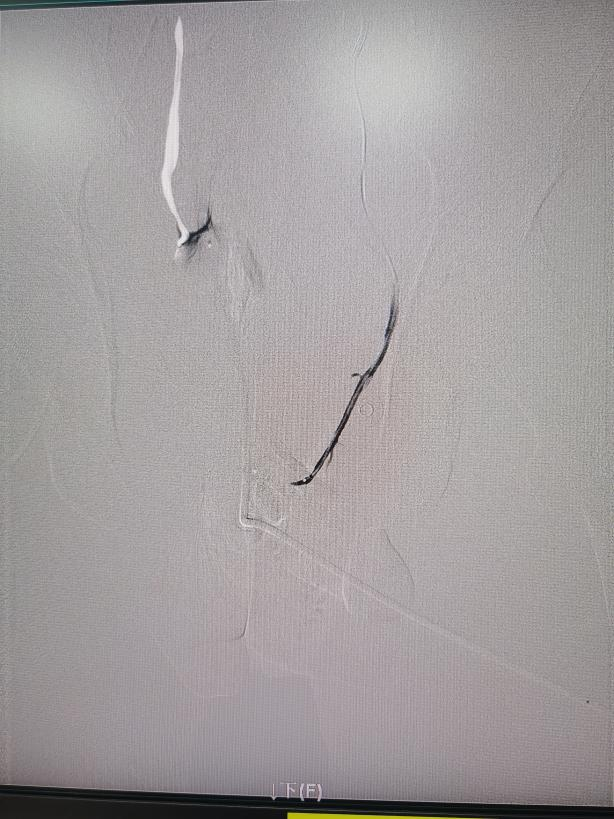

手术中,介入治疗医学中心主任罗阳带领医师林杰、李思刚,借助DSA影像实时引导,精准锁定左侧髂内动脉远端分支的出血点。

面对骨盆骨折后复杂的血管情况,专家们精细操作,如 “穿针引线” 般直达出血分支,用明胶海绵颗粒成功堵住 “漏水口”!术后造影显示,靶血管血流截断,外溢征象完全消失。出血完全停止,手术非常成功!

术后评估

术前后对比